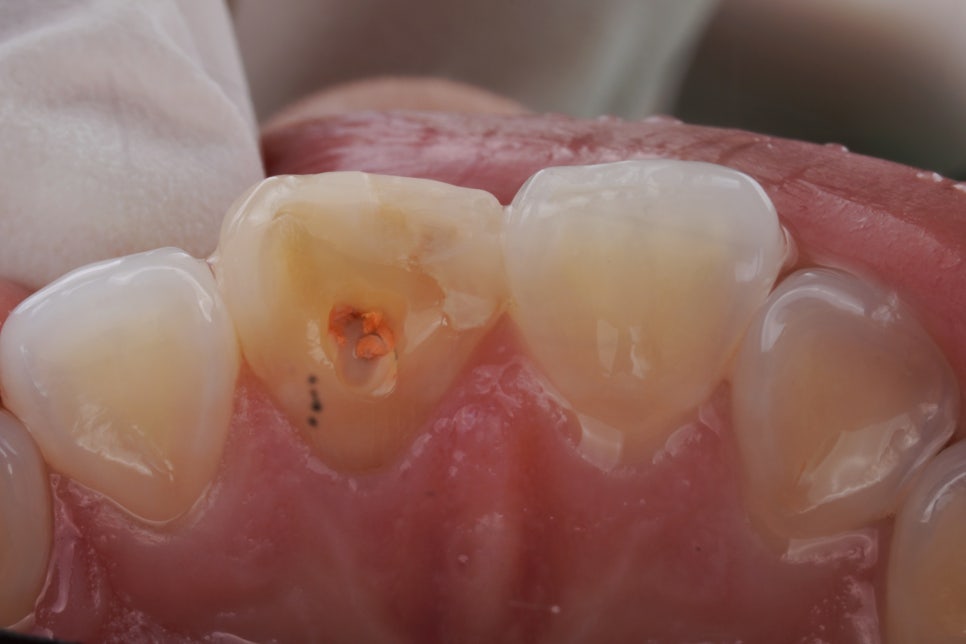

치아 안쪽에 약재를 넣어 진행하는데요. 과정을 간단히 설명드릴게요^^

먼저 신경치료가 되어 있는 치아를 열어서 안쪽 상태를 확인하는 과정을 거쳐요.

그리고 변색의 원인이 될 수 있는 신경관 입구 쪽의 약재나 충전물을 정리해 줍니다.

이 과정만으로도 색이 조금 밝아질 때도 있어요.

그다음에는 치아 내부 공간에 미백 약제를 넣어서 일정 시간 작용하도록 하는데요. 이 약제에서 산소가 발생하며 조금씩 밝게 만들어 주는 원리에요^^